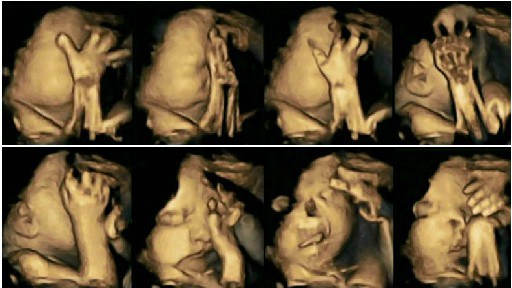

ภาพที่เห็นด้านบนนี้เป็นภาพการอัลตร้าซาวด์ 4 มิติ แสดงให้เห็นทารกที่คุณแม่ตั้งครรภ์ไม่ได้สูบบุหรี่ ซึ่งดูสุขภาพดีตามปกติ

ส่วนภาพด้านล่างนี้ เป็นภาพอัลตร้าซาวด์ 4 มิติ ที่แสดงผลของทารกในครรภ์ที่คุณแม่สูบบุหรี่

*ผลจากภาพอัลตร้าซาวด์ที่เกิดขึ้นคือ ทารกดิ้นรนใช้มือปัดและหันหน้าหนีเหมือนรู้สึกอึดอัด หายใจไม่ออก ทารกรับรู้ตั้งแต่อยู่ในครรภ์แล้วนะคะ และสิ่งนี้ทรมาณสำหรับทารกมากค่ะ*

สังเกตจากภาพอัลตร้าซาวด์จะเห็นว่าทารกในครรภ์ที่คุณแม่ที่สูบบุหรี่นั้นจะพยายามเคลื่อนย้ายใบหน้าของตัวเองเพื่อหลบเลี่ยง และบางภาพก็แสดงให้เห็นว่าทารกพยายามนำมือมาปิดปากปิดจมูกไว้ลักษณะเหมือนกำลังอึดอัด เพราะทารกได้รับรู้กลิ่นและรสสัมผัสได้ตั้งแต่อยู่ในท้องแล้วนั่นเองค่ะ อีกทั้งการเคลื่อนไหวร่างกายจะช้ากว่าทารกที่อยู่ในครรภ์คุณแม่ที่ไม่สูบบุหรี่อีกด้วย นี่เป็นผลตัวอย่างของคุณแม่ตั้งครรภ์ในจำนวน 20 คน ที่มักจะสูบบุหรี่วันละ 14 มวนต่อวัน